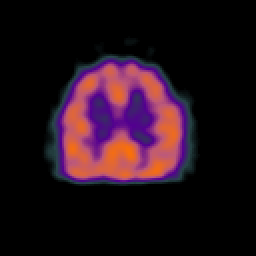

Normal aging, overlay -- Slice #38

[Home][Help][Clinical] Slice 38